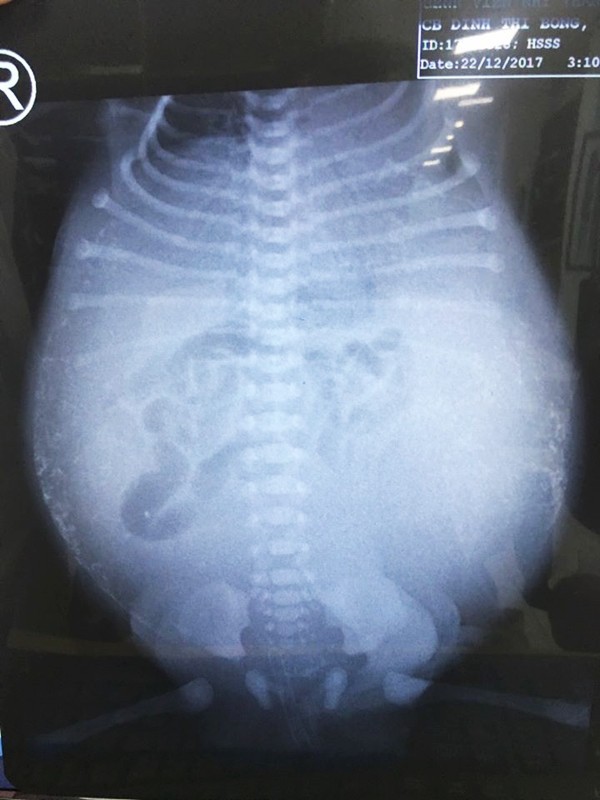

Ngày 10-1, bệnh viện (BV) Nhi đồng Thành Phố (huyện Bình Chánh, TP.HCM) cho biết, nơi đây vừa cứu sống trường hợp trẻ sơ sinh mang tình trạng nặng nề sau khi sinh.

Theo lời kể của bà ngoại, bé trai con một sản phụ ở thành phố Cần Thơ được chẩn đoán theo dõi thủng ruột do viêm phúc mạc bào thai, từ trong bụng mẹ lúc thai 25 tuần. Đến tuần thứ 36, diễn tiến thai kỳ sản phụ có nhiều nước ối, lại bị tăng huyết áp nên các bác sĩ (BS) quyết định chấm dứt thai kỳ. Sau chào đời, bé bụng trướng căng, suy hô hấp, xuất huyết toàn thân, được đặt ống thở.

Khi được chuyển đến BV tuyến trên, bệnh nhi đã suy hô hấp nặng, nhiễm trùng nhiễm độc nặng, bụng bé trướng căng như quả bong bóng sắp vỡ, xuất huyết toàn thân. Thành bụng bệnh nhi nhiều nơi xuất huyết, ọc ra máu miệng, trong ống thở có bọt máu. Trước bệnh nguy kịch này, các BS thăm khám xong đều lắc đầu, giải thích với gia đình rằng tiên lượng bé rất khó qua khỏi.

Sau 2 ngày hồi sức tích cực, đặt ống dẫn lưu ổ bụng tạm thời, ca phẫu thuật được tiến hành. Trước tình trạng bụng bệnh nhi đầy dịch phân, mủ, thủng ruột non, viêm toàn bộ ổ bụng ekip mổ phải đưa tạm một lỗ ruột ra ngoài để giải áp chứ không nối ruột ngay được.